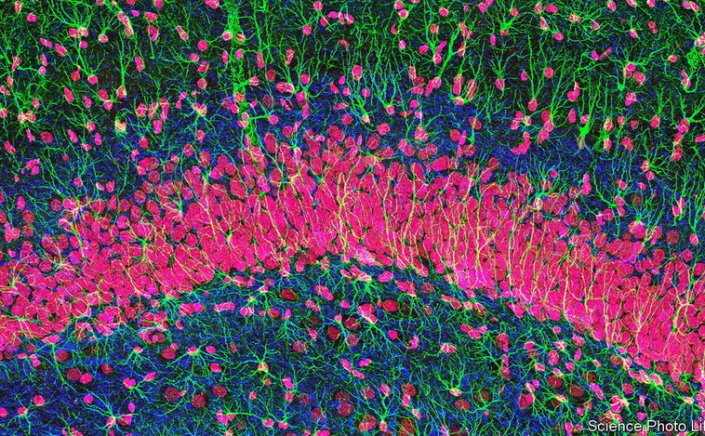

Brain Cells: Οι νευρώνες δεν είναι τα μόνα εγκεφαλικά κύτταρα που σκέφτονται

Brain Cells / Τα αστροκύτταρα, για παράδειγμα, μπορεί να παίζουν ρόλο στην κατάθλιψη και το άγχος.